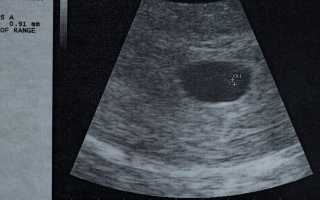

Диагностика патологии осуществляется с помощью ультразвукового исследования полости матки и её придатков.

На сроке 6 недель врач-диагност может обнаружить плодное яйцо. Однако определить, есть ли в нем жизнь, невозможно из-за небольшого срока беременности. Женщине рекомендуется повторить исследование не ранее чем через 2 недели.

Не стоит полагаться на результаты лабораторных анализов уровня ХГЧ, так как этот гормон может повышаться как при анэмбрионии, так и при внематочной беременности. К сожалению, до 8 недель беременности поставить диагноз невозможно.

При проведении трансвагинального ультразвукового исследования врач может определить наличие эмбриона в яйце. Если результаты вызывают сомнения, исследование повторяется через месяц.